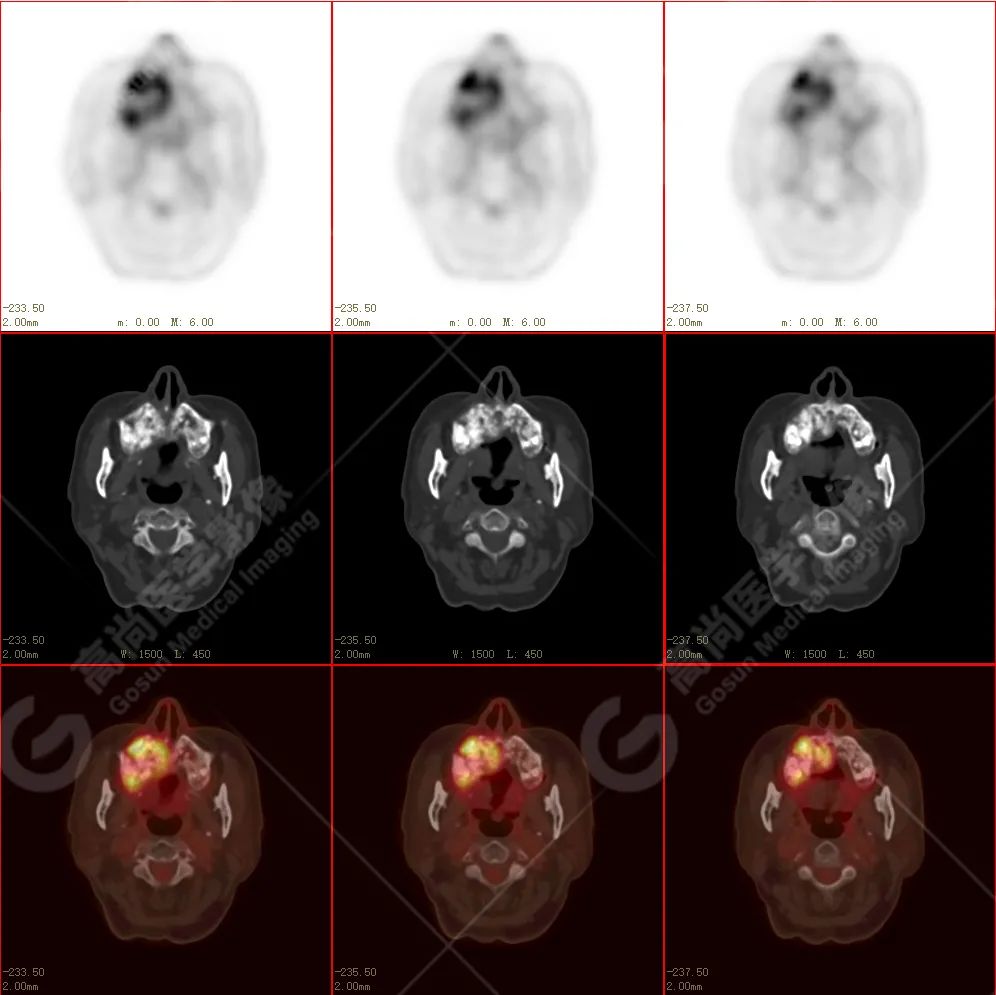

右侧上颌骨-上颌窦骨壁-骨性鼻中隔区域见片块状放射性摄取异常增高影,最大层面约 4.1 cm×3.8 cm×2.8 cm,SUV 最大值为 10.4,CT 示上述部位见成骨性改变,骨质不均匀弥漫性增厚、密度不均匀增高,并可见肿瘤骨影,边缘毛糙,周围伴软组织增厚。

根治性手术在放疗后骨肉瘤的治疗中是必须的,然而根治性手术仅仅适用于早期的病例,如本例病人,相对早期,周围组织结构无明显侵犯,PET 示肿瘤代谢也局限于肿瘤本体。